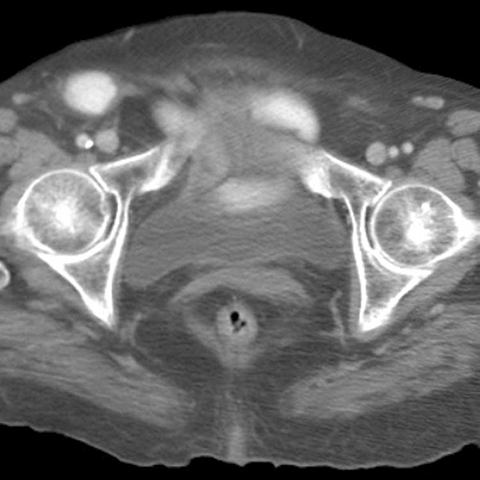

77 year-old woman presents with abdominal pain,vomiting, fever, and tachycardia [2 of 3]